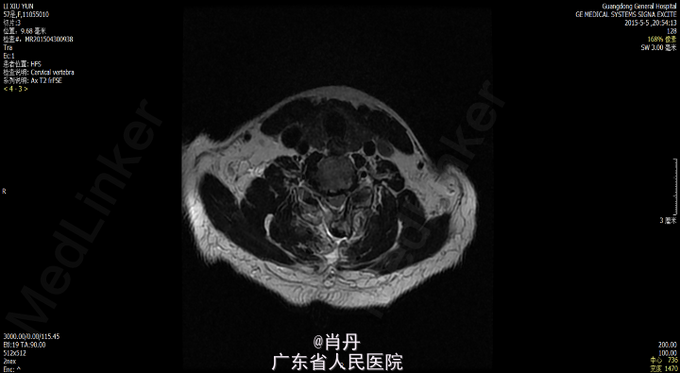

患者女,57岁,因“双上肢麻木8年加重伴双下肢行走不稳2年”入院。8年前开始出现双上肢麻木感,逐渐加重,一直未诊治,2年前开始出现行走不稳,行走踩棉花感,近几个月来不能独立行走,需要搀扶。入院临床诊断:脊髓型颈椎病。

查体双上肢皮肤触痛觉减退,四肢肌力正常,四肢肌张力增高,四肢病理征阳性,深反射亢进。X光CT,MR如下,C5~C6后纵韧带骨化,继续性颈椎管狭窄,相应平面脊髓变性。JOA 7 分(17分法)

诊断:脊髓型颈椎病,颈椎后纵韧带骨化症;处理:一期颈椎后路C3-7单开门,二期颈椎前路C5-6椎体次全切除。一期颈椎后路术后JOA由 术前的7分改善到11分,二期颈椎前路手术后改善到13分。